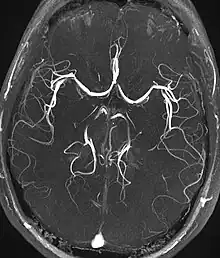

Magnetic resonance angiography (MRA) generates pictures of the arteries to evaluate them for stenosis (abnormal narrowing) or aneurysms (vessel wall dilatations, at risk of rupture). MRA is often used to evaluate the arteries of the neck and brain, the thoracic and abdominal aorta, the renal arteries, and the legs (called a "run-off"). A variety of techniques can be used to generate the pictures, such as administration of a paramagnetic contrast agent (gadolinium) or using a technique known as "flow-related enhancement" (e.g., 2D and 3D time-of-flight sequences), where most of the signal on an image is due to blood that recently moved into that plane (see also FLASH MRI).[39]

Techniques involving phase accumulation (known as phase contrast angiography) can also be used to generate flow velocity maps easily and accurately. Magnetic resonance venography (MRV) is a similar procedure that is used to image veins. In this method, the tissue is now excited inferiorly, while the signal is gathered in the plane immediately superior to the excitation plane—thus imaging the venous blood that recently moved from the excited plane.[40]

| Magnetic resonance angiography (MRA) and venography | Time-of-flight | TOF | Blood entering the imaged area is not yet magnetically saturated, giving it a much higher signal when using short echo time and flow compensation. | Detection of aneurysm, stenosis, or dissection[80] | ![]() |